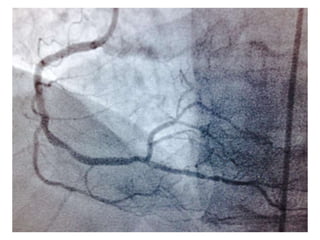

CUADRO CLINICO: INFARTO AGUDO DEL MIOCARDIO CON ELEVACION ST DE

LOCALIZACION ANTERIOR EXTENSO. REFERIDO DESDE JUIGALPA A LAS 8 HORAS

DESPUES DEL EVENTO

TA 110/ 50 mm Hg. FC 117/min Fr 19/ min

Glucosa 245 mg /dL. Colesterol total 277 mg/dL, LDL 170 mg d/L

Creatinina 1.6mg/dL. Marcadores cardiacos de daño miocárdico elevados

EXAMEN FISICO: Killlip KimbalI II.

CLINICAMENTE CON ANGOR E INESTABILIDAD HEMODINAMICA

CASO CLINICO #2 MASCULINO 70 AÑOS DE EDAD GANADERO, ACTIVO FISICAMENTE DIABETES TIPO 2 DESDE HACE 15 AÑOS. CONTROL METABOLICO POBRE HIPERTENSION ARTERIAL CONTROLADA CON ATENOLOL. CUADRO CLINICO: INFARTO AGUDO DEL MIOCARDIO CON ELEVACION ST DE LOCALIZACION ANTERIOR EXTENSO. REFERIDO DESDE JUIGALPA A LAS 8 HORAS DESPUES DEL EVENTO TA 110/ 50 mm Hg. FC 117/min Fr 19/ min Glucosa 245 mg /dL. Colesterol total 277 mg/dL, LDL 170 mg d/L Creatinina 1.6mg/dL. Marcadores cardiacos de daño miocárdico elevados EXAMEN FISICO: Killlip KimbalI II. CLINICAMENTE CON ANGOR E INESTABILIDAD HEMODINAMICA